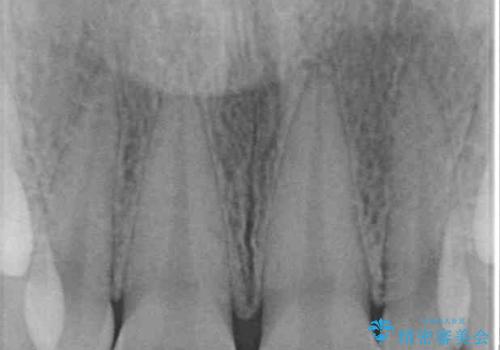

- 前歯の矮小歯と捻れや変色を気にして来院された患者様です。

結婚式が近いということもあり、前歯4本をオールセラミッククラウンにて補綴治療することとしました。

前歯の捻れは、オールセラミッククラウンよりも矯正治療による改善の方が、歯を削らなくて済むためお勧めとなります。

しかし、矮小歯の改善はオールセラミッククラウンでの補綴治療が必要であり、幅径のバランスを取る必要があるため、4前歯の補綴治療を選択しました。